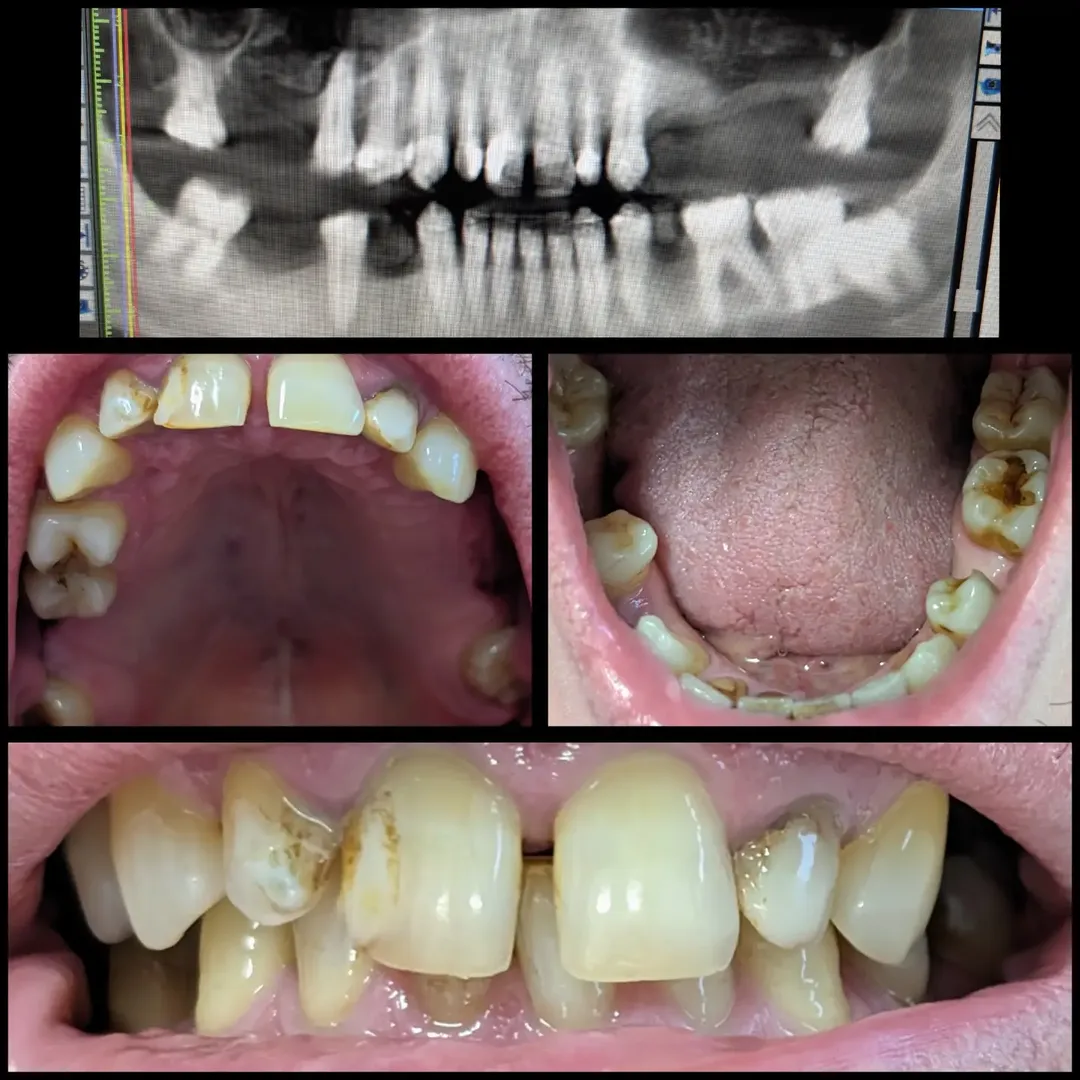

Situação inicial

O paciente apresentava ausências dentárias em ambos os quadrantes superiores e na arcada inferior, com múltiplos dentes comprometidos. A ortopantomografia e o CBCT confirmaram seios maxilares muito baixos, com osso insuficiente para a colocação de implantes nas zonas posteriores superiores.

- Arcada inferior - Planeamento digital e cirurgia guiada: Realizei o planeamento digital com CBCT e scans intraorais, e avancei com cirurgia guiada para a colocação de 3 implantes, devolvendo a carga mastigatória total na arcada inferior.

Nas imagens, é possível ver a evolução desde a situação inicial com múltiplas ausências e dentes comprometidos, até ao resultado final com todas as zonas reabilitadas. O paciente recuperou a função mastigatória completa e uma estética natural, sem ter de usar uma prótese removível.